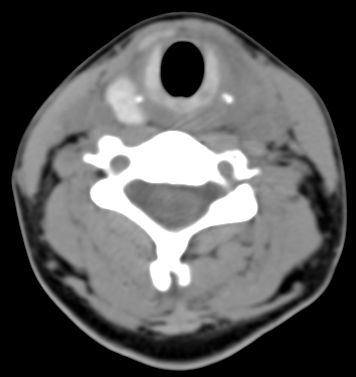

标题: CT9717:F、30Y、颈部左侧包块半年,压痛.患者拒绝作增强。 [打印本页]

标题: CT9717:F、30Y、颈部左侧包块半年,压痛.患者拒绝作增强。

请各位老师帮忙看看左侧甲状腺病灶!

甲状腺弥漫增大,以左叶明显,内见不均匀低密度影,边缘模糊欠清,周围脂肪间隙模糊。

结合病史:考虑亚急性甲状腺炎可能性大。(不知道病人有没有检测tsh t3 t4)

左侧甲状腺及甲状腺狭部弥漫性增大,边缘模糊,未见明确界线.考虑甲状腺炎可能性大.

左侧甲状腺弥满性增大,其内密度均匀减低,气管无受压。周围结构清晰。考虑甲状腺炎可能性大。

甲状腺弥漫增大,以左叶明显,左侧内见不均匀低密度影,边缘模糊欠清,周围脂肪间隙模糊。